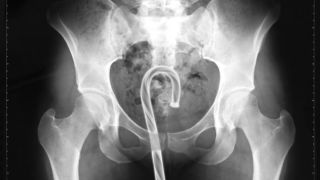

Penis

- COAT HANGER